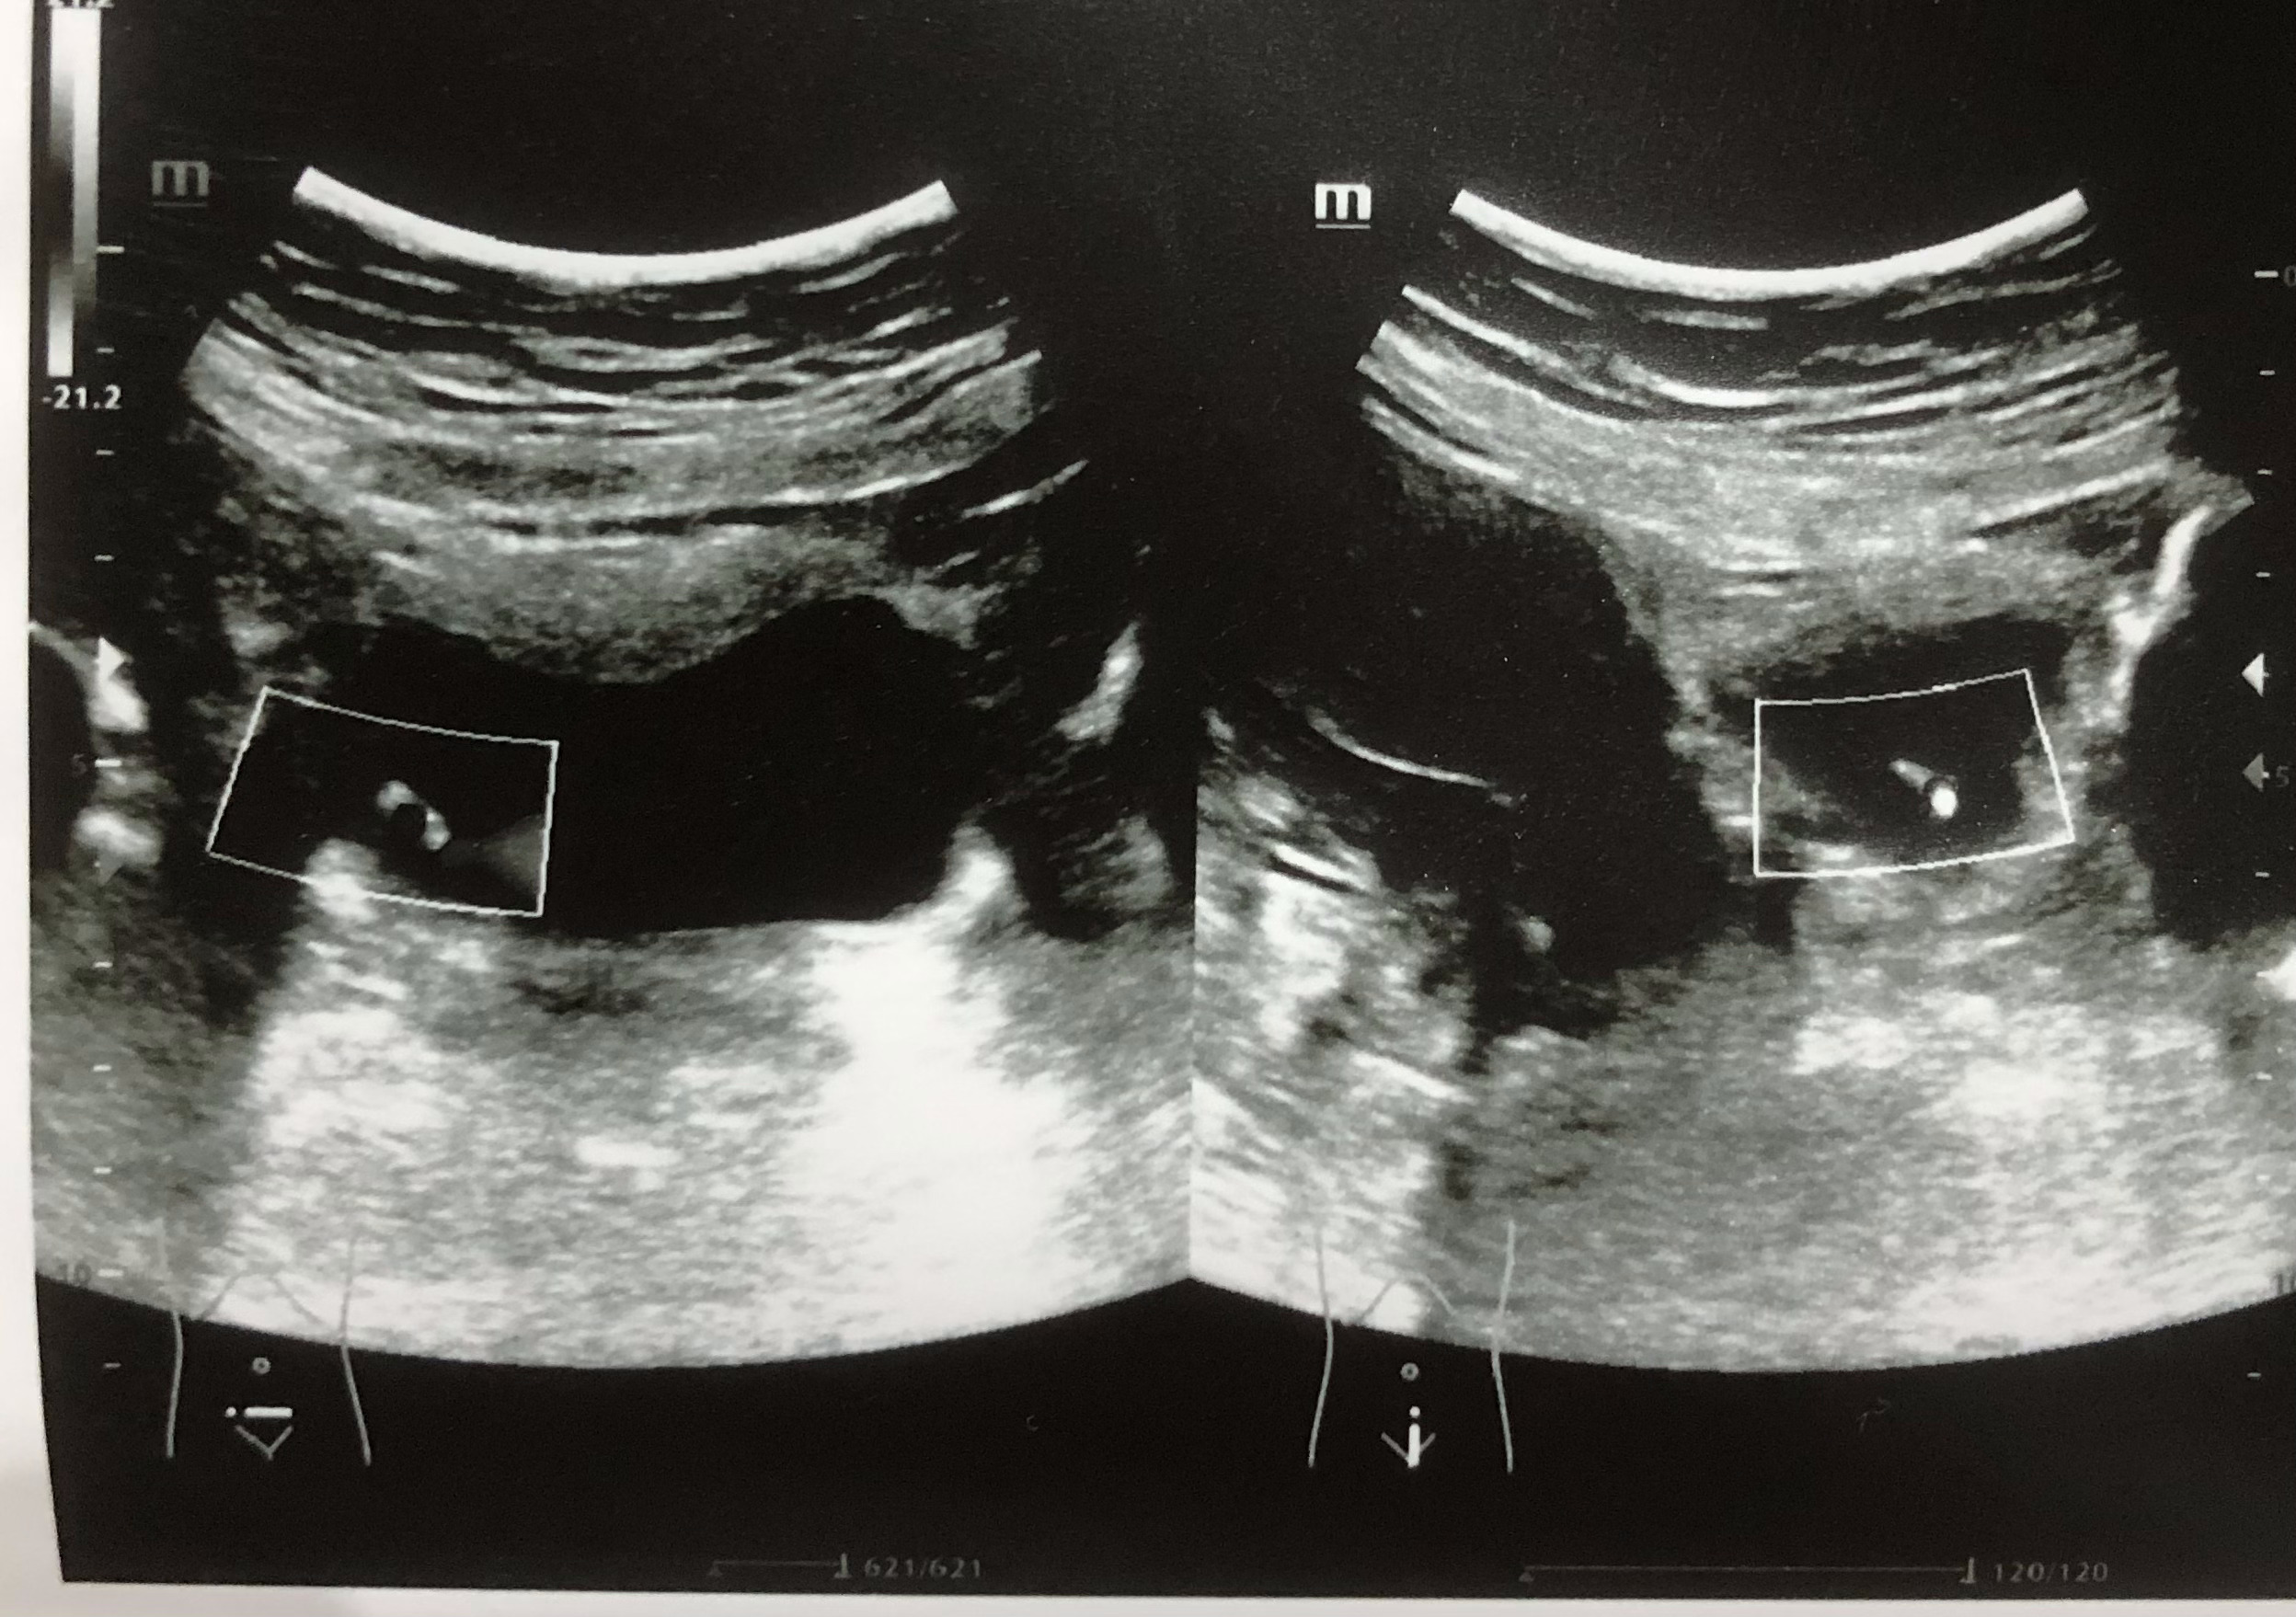

Se realiza ecografía renal donde se aprecia lesión hiperecogénica redondeada en pared inferior derecha de vejiga sin sombra posterior de 0,7 x 0,61 cm, que no se moviliza con cambios posturales de la paciente. Centelleo dudoso.

Litiasis vs lesión de características malignas.

Se realiza citoscopia y deciden resección transureteral con resultado de anatomía patológica de carcinoma urotelial de vejiga.